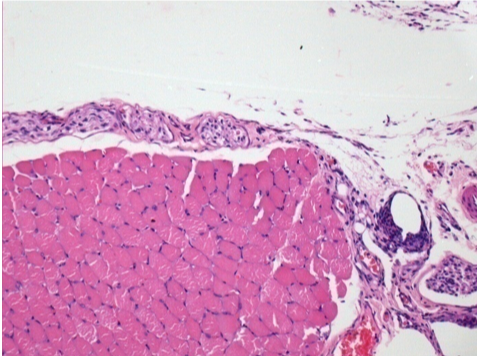

1 mes después de la inyección de Endopeel 0,1 ml en el músculo pretibial derecho.

¡Lo que se ve en negro en las imágenes no es una necrosis como podrían imaginar algunos científicos!

De hecho, hay que tener en cuenta 4 conclusiones